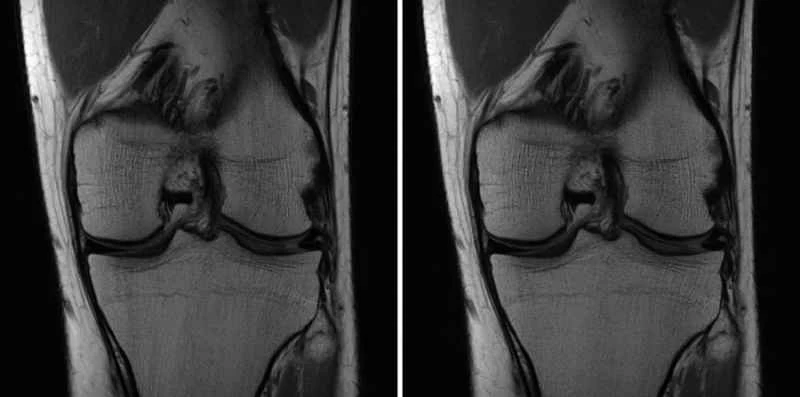

By記事2026-01-04 フェイスブックが人工知能を使ってMRIスキャンを高速化する取り組みを独占取材 ジーナ・シアヴァラは、マンハッタンにあるニューヨーク大学ランゴン・ヘルスの暗い部屋に座っている。そこは読影室で、彼女のような放射線科医がX線やMRIのスキャン画像を検査する場所だ。目の前のモニターには、匿名化された患者の膝のグレースケール画像が映し出されており、彼女はそこに一つの重大な問題を発見した... 記事